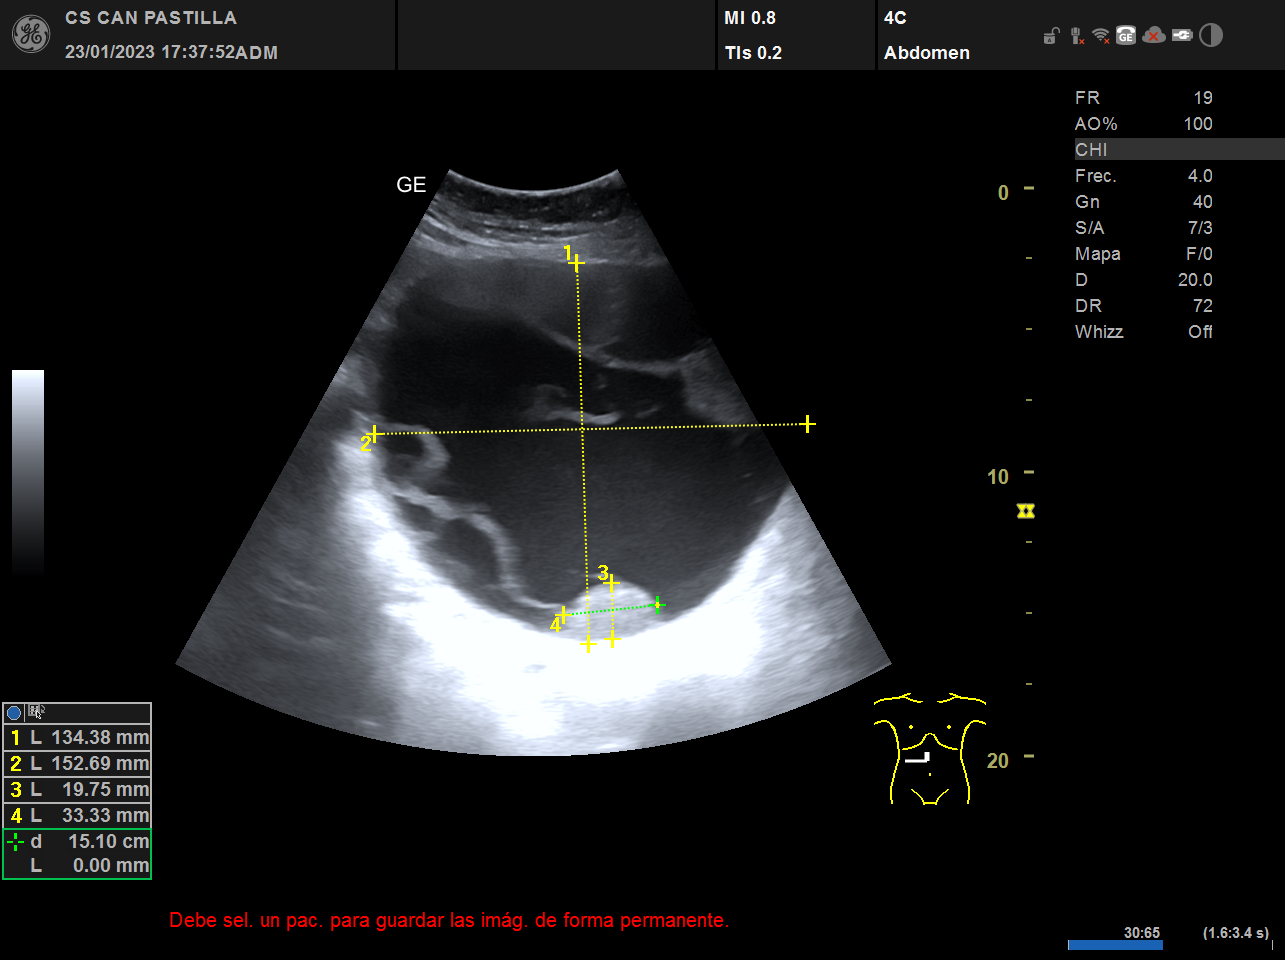

ECO abdominal: destacan imágenes anecóicas con refuerzo acústico posterior y septos en su interior, sugestivas de quistes complejos de gran tamaño (el mayor de ellos de 15 cm de diametro) o un solo quiste tabicado de gran tamaño. Dificultad para observar el parénquima hepático de forma completa, dados la ocupación de las imágenes quísticas.